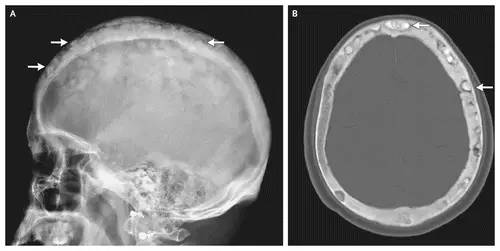

棉絮征—佩吉特骨病

棉絮征

今天下班回家的路上看到一个买棉花糖(Cotton candy)的摊子,回来的时候就想到写一下“Cotton wool”这个征象,典型的棉绒征在国内应该不算常见,今天讲到的棉絮征是Paget(佩吉特)骨病中局限性钙质沉着在疏松的颅骨骨质中呈类似棉絮样改变的征象。

影像特点

佩吉特骨病的X线检查通常具有诊断意义并且可评估治疗后的临床疗效。

X线可表现出病变处皮质增厚、骨增粗、溶骨和骨硬化同时存在的现象、粗糙的骨小梁等。长骨受累及早期可由一端的软骨下骨开始发病,延伸至骨干的不同部位,出现病变与正常结构的分界,如V形裂解区(“火焰”或“割草刀片”影像学改变)。负重部位的骨骼则可出现弯曲及骨皮质出现小的裂隙骨折,尤其是股骨病变时凸面的病理性骨折明显。

随着时间的推移病变可发生变化,治疗后溶骨区域可逆转。则某些特殊区域佩吉特骨病可出现特征性的改变,如脊柱受累时可出现“窗户框”现象,骨盆受累时可出现髋臼内陷及骶髂关节关节强直,颅骨受累时可出现骨质疏松性局限性钙质沉着和颅底凹陷症。